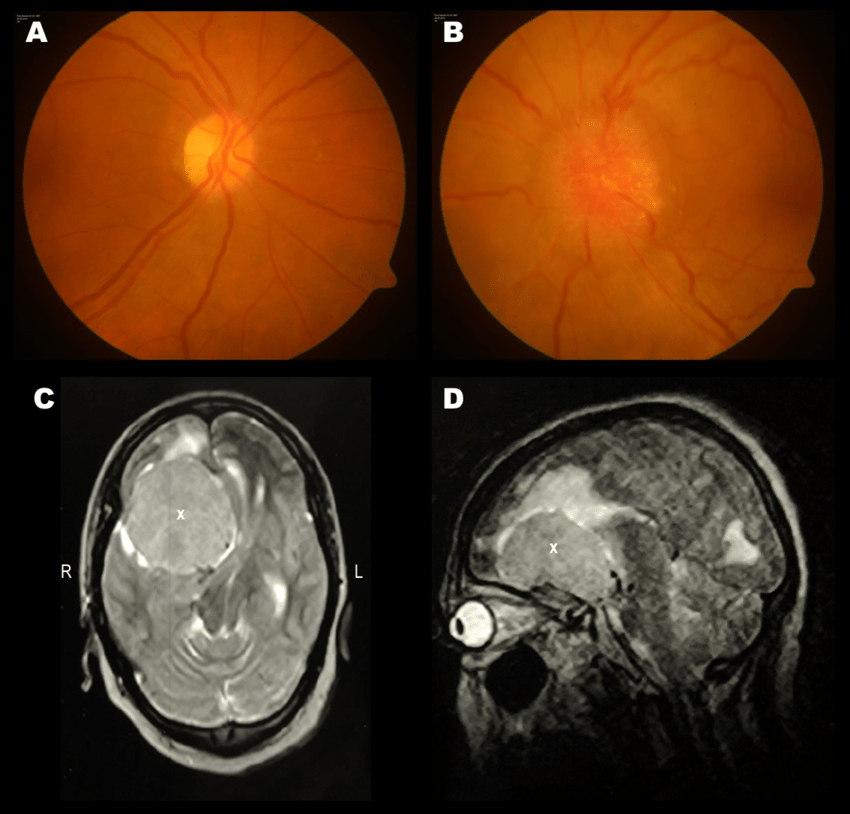

Foster Kennedy syndrome is a constellation of signs attributed to brain tumor located in the anterior skull. The condition is characterized by ipsilateral optic atrophy secondary to compression. In addition, contralateral papilledema is present. Reference: Bailey and Love's Short Practice of Surgery Image via: https://www.researchgate.net/figure/Foster-Kennedy-Syndrome-in-a-52-year-old-woman-A-Fundus-picture-of-the-right-eye_fig1_330713983